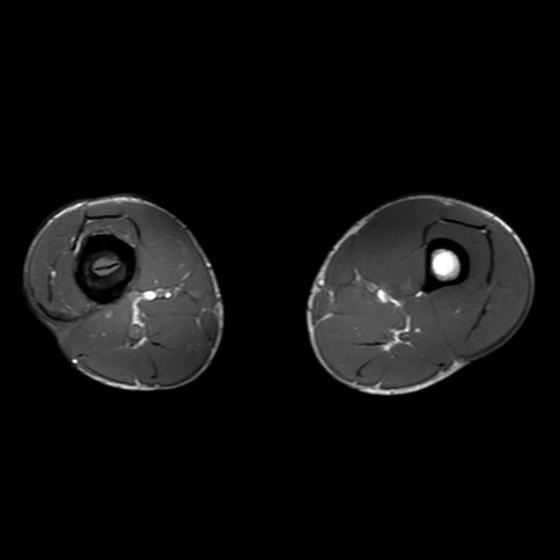

Viêm xương tủy mạn tính (Chronic osteomyelitis)

16/03/2026